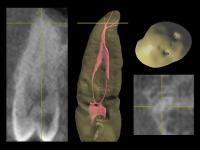

- • Горизонтальный срез на границе апикальной трети (рис. 64-66): обнаруживается щелевидная форма и объединение корневых каналов 1.5 зуба в один.

- • Горизонтальный срез в 2 миллиметрах от апекса (рис. 67-68): корневые каналы опять раздваиваются.

| Рис. 64-66 Профильные срезы и 3-D визуализация апикальной трети 1.5 зуба: корневые каналы сливаются |

| Рис. 67-68 Профильные срезы и 3-D визуализация в 2 мм от апекса: корневые каналы расходятся |

• Ниже (рис. 75-76) представлены фрагменты профильных срезов, наглядно показывающие зоны объединения (устьевая часть, апикальная треть) и расхождения (средняя треть, апекс) корневых каналов 1.5 зуба, а также пример подобной системы из Dental Anatomy & Interactive 3-D Tooth ATLAS (Brown and Herbranson).

| Рис. 75 Обтурация корневых каналов, данные томограммы и 3D диагностики |

Рис. 76 Пространственная иллюстрация эндо-системы (3-D Interactive Tooth ATLAS) |